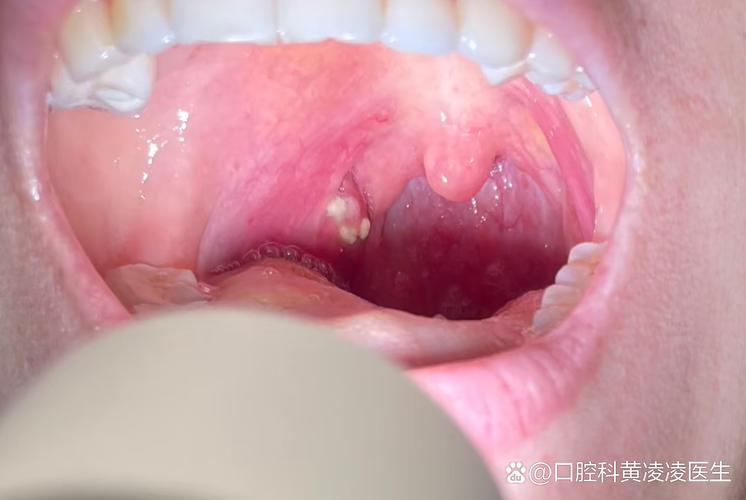

粘液腺囊肿:

- 描述:由于唾液腺导管被堵塞,导致分泌物潴留,形成一个充满粘液的小囊肿。

- 特点:通常表现为一个半透明或淡蓝色、柔软的、像水泡一样的小凸起,大小可能变化,如果破裂,会流出粘稠液体,然后可能再次长出,一般不痛,但如果继发感染会疼痛。